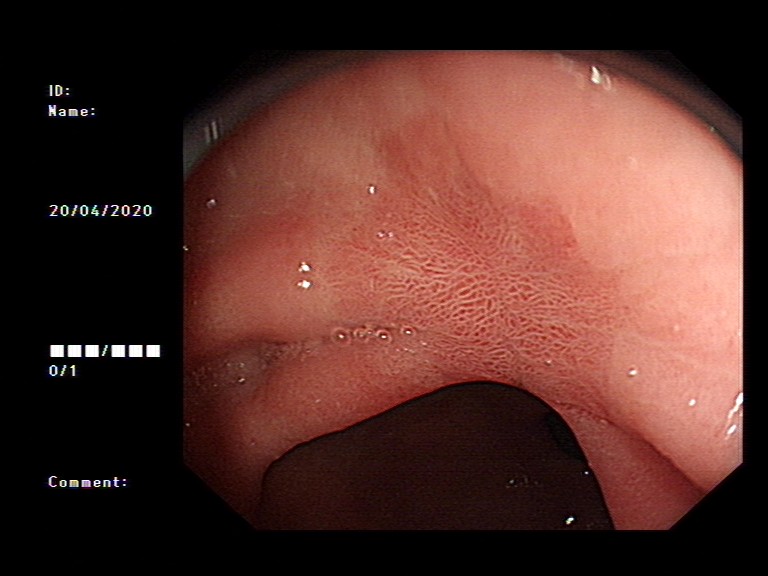

2020年1月,元旦刚过,大家都还沉浸在新年的喜悦中,来自隆安县的张阿姨一家却一筹莫展,张阿姨今年55岁,半年前开始出现上腹部胀痛不适,在当地医院一直按“慢性胃炎”服用中药及西药治疗,症状时好时坏。为了进一步治疗,来到我院就诊,内镜中心袁海锋主任亲自为其进行了无痛胃镜检查,经认真仔细观察发现胃内一处凹陷型病变,进一步行精细胃镜检查后,初步判断为早期胃癌病灶,而且病变侵犯深度局限在粘膜层内。经过与张阿姨及家属详细沟通后,决定用内镜下微创手术为其治疗。在内镜下确定病变边界后,顺利行内镜下粘膜剥离术(ESD)将病变完整切除。术后标本病理提示:早期胃癌(中分化管状腺癌)。治疗后一周,恢复良好,顺利出院,至今随访未诉明显不适。对于张阿姨一家来说,得了胃癌很不幸,但不幸中的万幸,她的胃癌被我们早期及时发现并完成了内镜下切除,避免进展为中晚期胃癌,使原本不富裕的家庭再雪上加霜。

图2 ESD术及术后标本